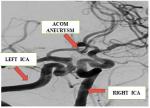

- The head angiography CT show only an wide neck aneurysm of the left internal carotid artery( posterior communicating artery segment)

- The cerebral DSA show an ruptured wide neck aneurysm of ACOM artery; two unruptured wide neck aneurysm of the left internal carotid artery (posterior communicating artery and ophthalmic artery segment).

- An ruptured wide neck ACOM aneurysm treated with stent SILK V 2.75x15 from A1 to A2 of left ACA across ACOM artery. After that coils were deployed over a microcatheter from right ACA into ACOM artery across the neck of the ruptured aneurysm.